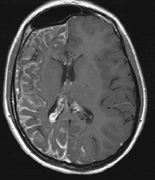

STURGE-WEBER SYNDROME Sturge (1879) reported the case of a child with facial “port-wine stain,” epilepsy, buphthalmos, and a dark choroid.204 Schirmer had noted the association of the facial vascular malformation and glaucoma in 1860.3 Weber (1922) reported brain X-ray findings of parallel streaks (“railtrack” sign), which he interpreted to represent calcific changes (Fig. 19).205